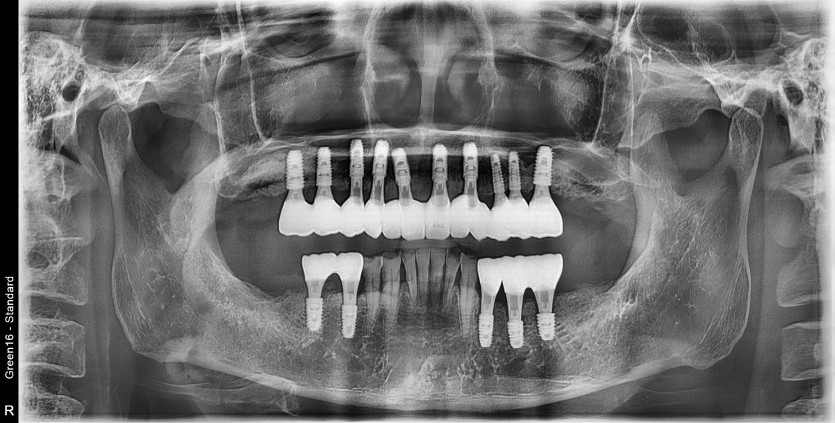

만 60세 상악 전체 임플란트 증례(기존 임플란트 활용)

상악 전체 임플란트 증례입니다.

(타원 임플란트 활용)(하악 일부)

12개의 임플란트로 완성하였습니다.